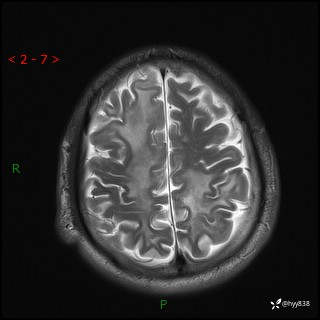

辅助检查:MRI

MRI T2WI